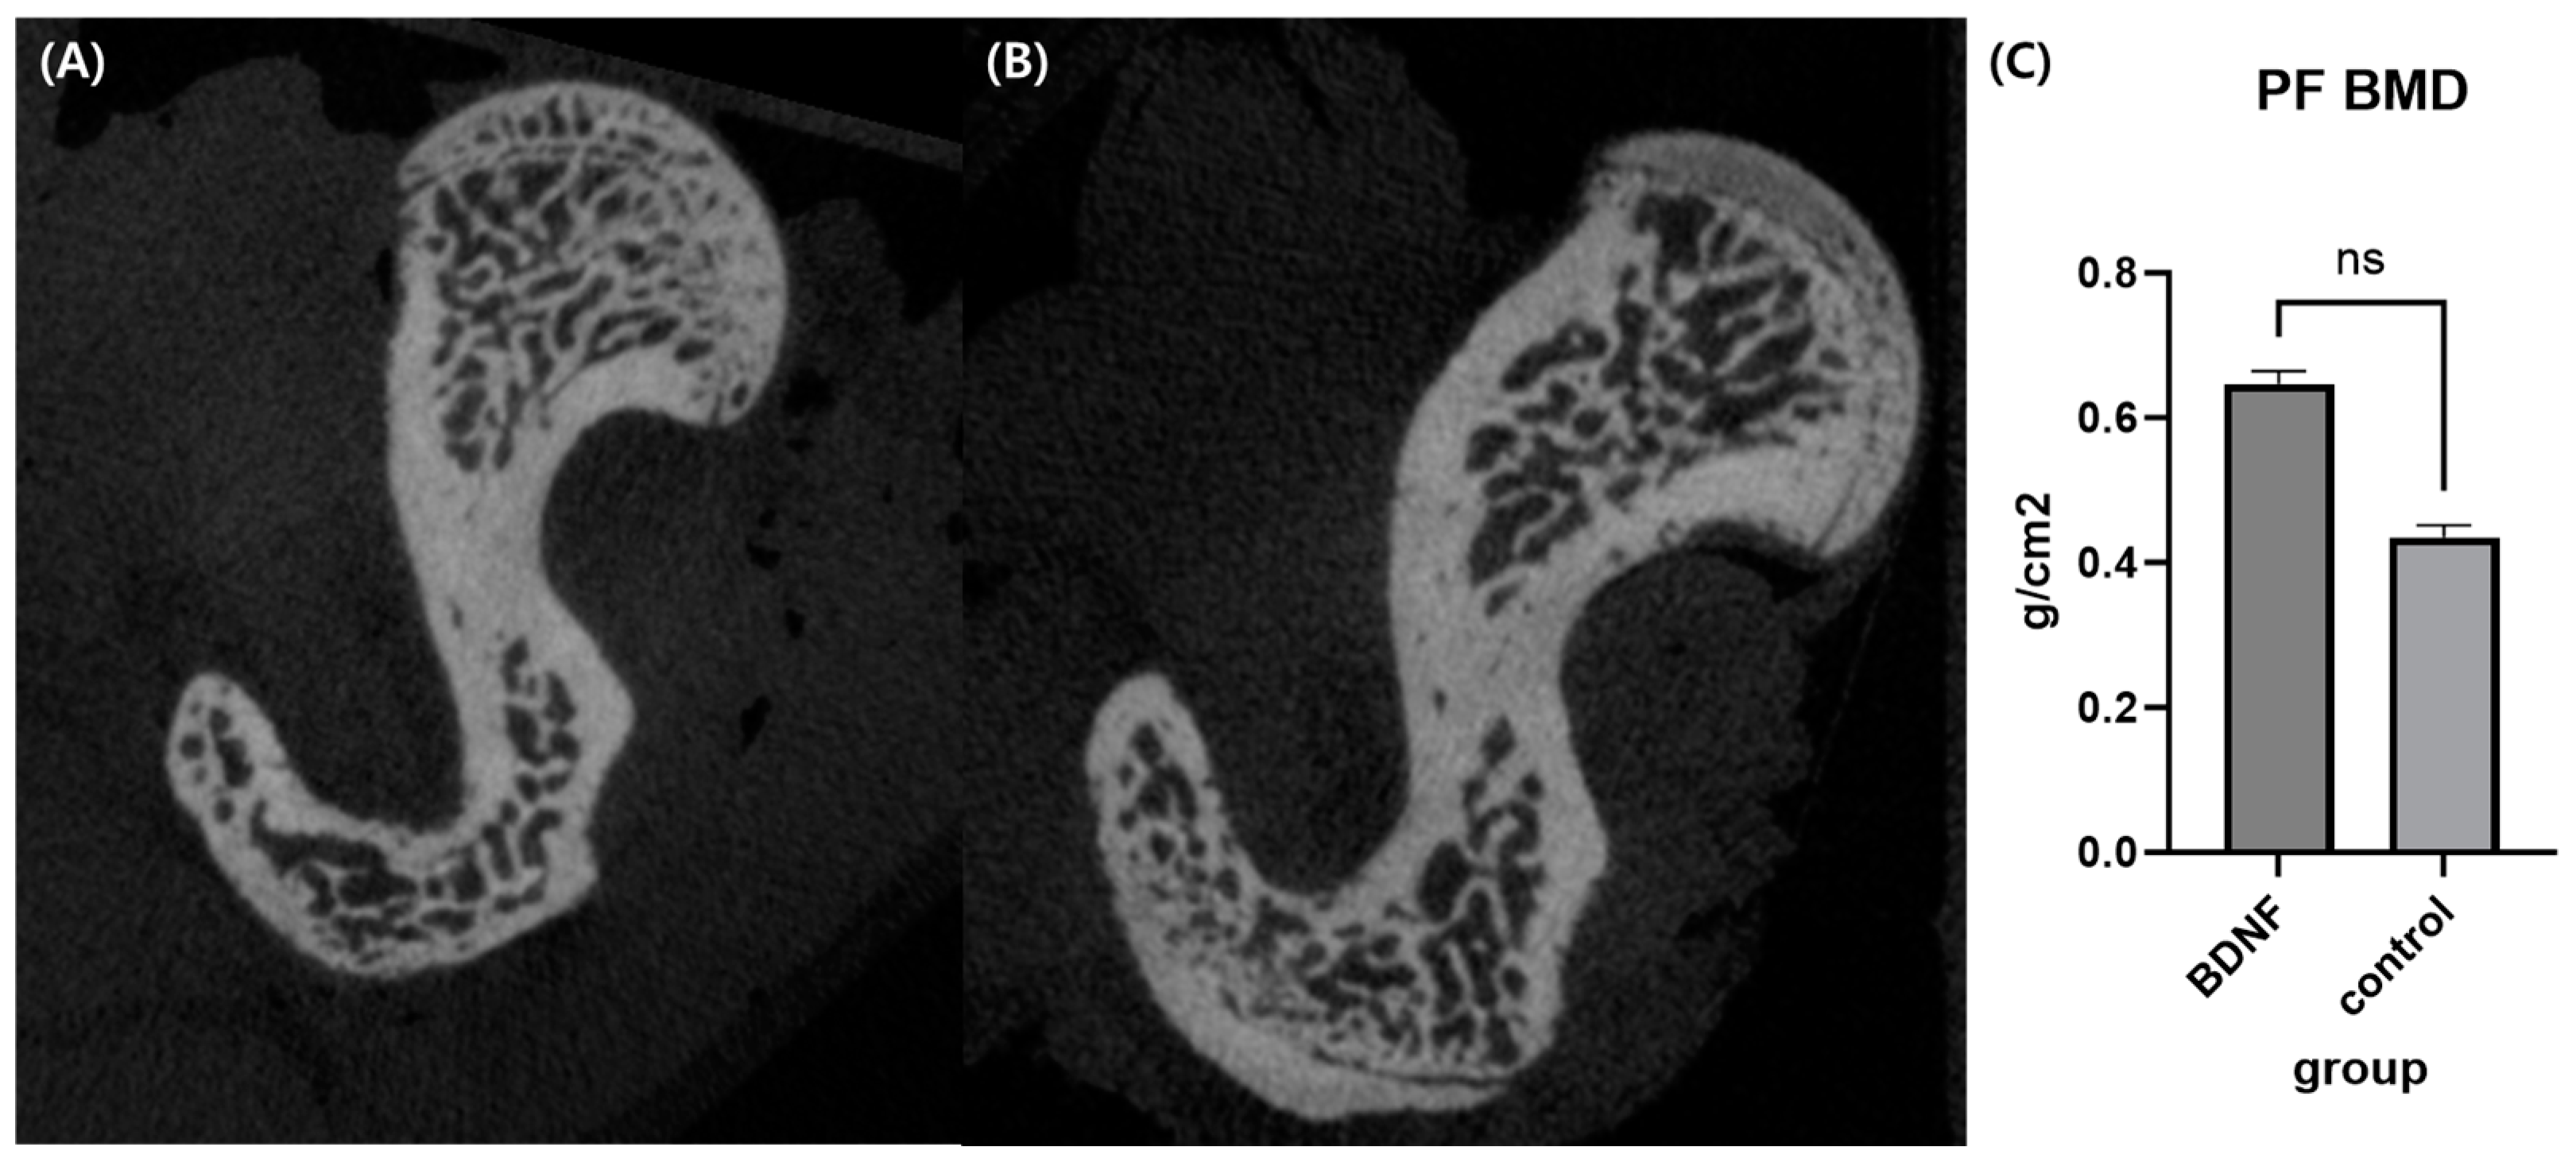

Micro-CT analysis showed that the bone mineral density of the BDNF group was higher compared to the control group but statistically not significant (Figure 6).

Figure 6.

Micro-CT analysis. Representative axial cuts of proximal femur of BDNF (A) and control group (B). (C) Comparison of bone mineral density between BDNF and control group. ns, non-specific; PF, proximal femur; BMD, bone mineral density.

Recently, BDNF has been reported to stimulate osteoblast differentiation of osteoblast-linage cell MC3T3-E1 and human bone mesenchymal stem cells and enhance the expression of osteogenesis-related markers, such as ALP and osteocalcin [18,27]. BDNF also upregulates the expression of bone/cementum-related proteins, including ALP, OPN, and BMP-2 in cementoblasts [28]. However, the effects of BDNF on osteoblast differentiation in bone marrow stromal cells and osteoporotic conditions, as well as its detailed mechanisms, have not been fully investigated. In this study, we focused on the investigating effects of BDNF on osteoblast differentiation in stromal cells and co-culture systems and associated bone formation signaling via MAPKs and TrkB receptors. We found that BDNF promoted osteoblast differentiation via the activation of the TrkB receptor along with the JNK and p38 MAPK signaling pathways. In vivo, this study failed to show significant improvement in bone density compared to the control group. We assume that the limited sample size led to such a result, although the BDNF group showed higher bone density, a higher osteoblast number, and a lower osteoclast number. A future study with a larger sample size focusing on bone microarchitecture and bone turnover markers is necessary to conclude our preliminary findings in OVX rats.